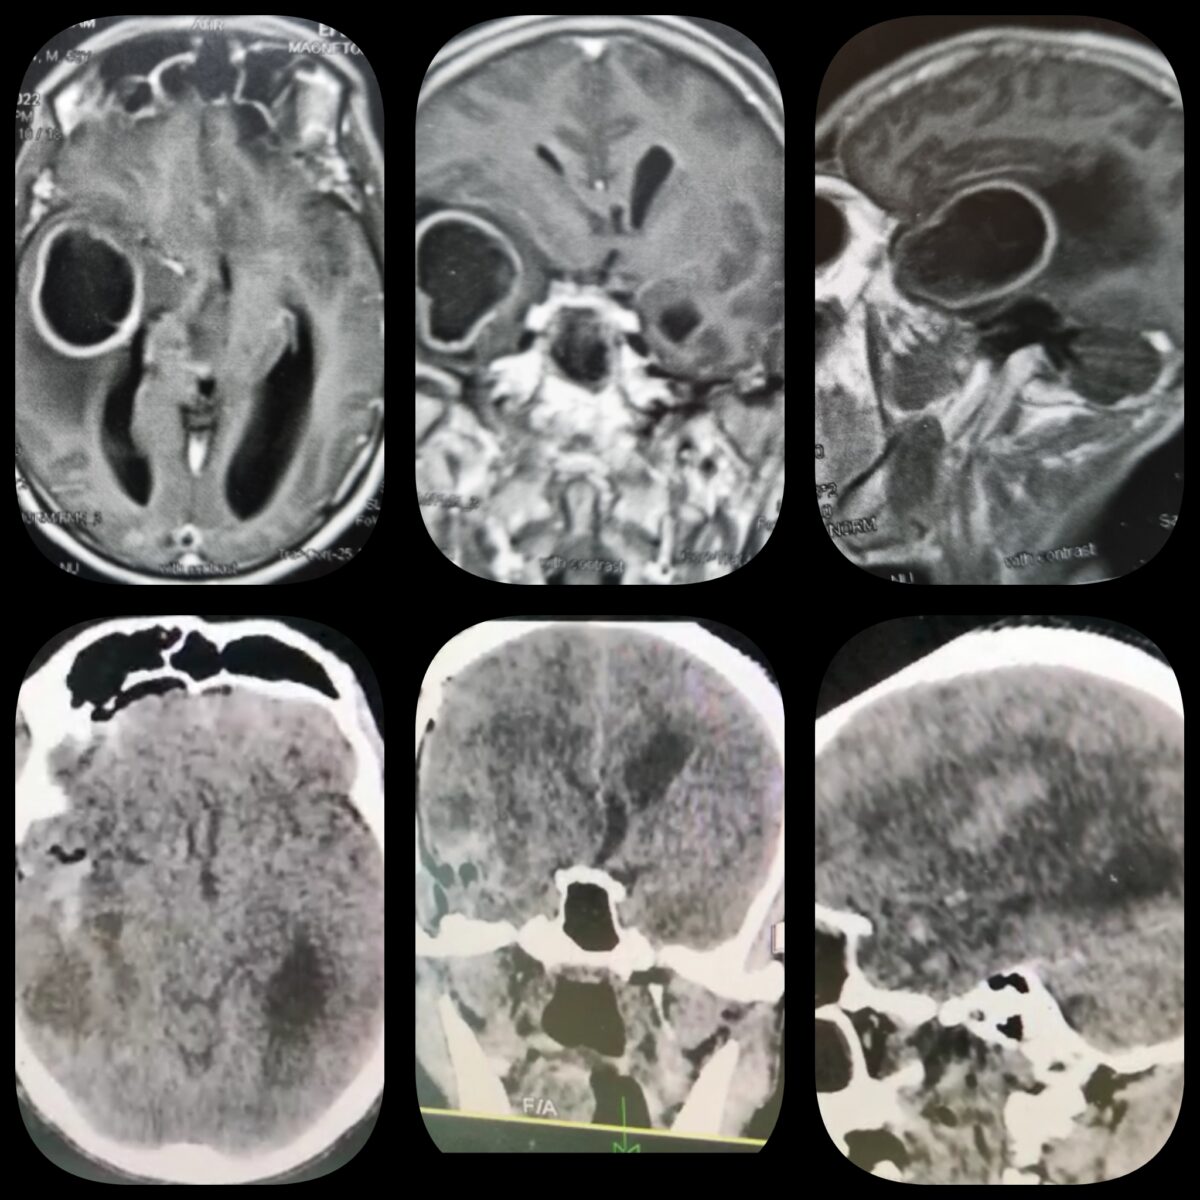

– الرنين المغناطيسي على المخ بالصبغة، والذي يظهر مكان الورم، ويساعد في التخطيط للجراحة، ويساعد في معرفة طبيعة الورم.

– الرنين المغناطيسي الطيفي، والذي يساعد في معرفة طبيعة الورم ودرجته من حيث قدرته على النمو والارتجاع بعد الجراحة.

أمثلة لاستئصال أورام داخل نسيج المخ بالجراحة الميكروسكوبية